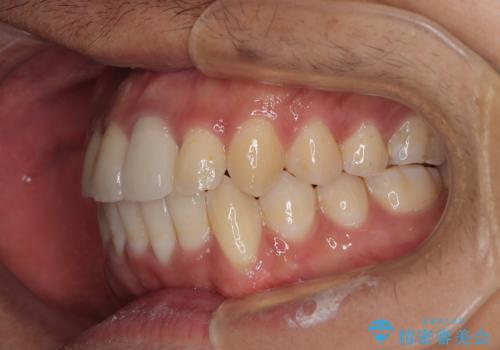

矯正治療後には気になっていた前歯をセラミッククラウンにし、自然な口元に仕上げることができました。